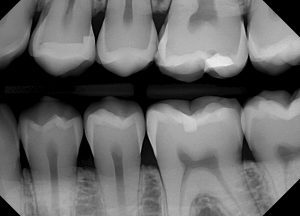

عکس رادیولوژی دندان بایت وینگ

گاهی اوقات به آنها “عکس رادیولوژی چکاپ دندان” می گویند. در این تکنیک یک تکه کاغذ را گاز میگیرید تا دندانپزشک بتواند وضعیت تماس تاج دندانها با یکدیگر را خوب ببیند. این عکس بیشتر برای تشخیص پوسیدگی بین دندانها استفاده می شود. آنها پوسیدگی بین دندان های شما و شروع پوسیدگی زیر پرکردنی ها را نشان میدهد و همچنین، از دست دادن و تحلیل استخوان فک را بررسی می کنند.